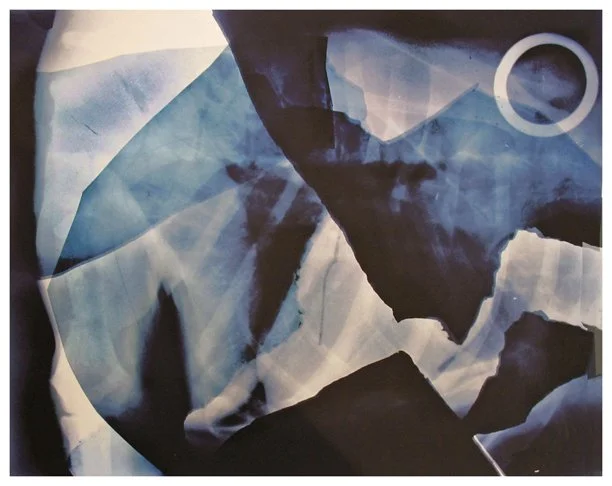

Insight is a series of collaged X-ray fragments, which were digitally composed into giclée prints. They speak not only of the body’s interior, but of the human experience it contains.

Drawn from DNA sequencing gels, mammograms, ultrasound scans, and cell cultures grown in Petri dishes, these compositions reframe diagnostic materials as metaphoric landscapes. What once served to identify illness becomes a language of line, texture, and light. They serve as a quiet meditation on fragility, resilience, and the unseen forces that shape us.

Each image in Insight is both an anatomical artifact and an artistic inquiry. Each one is part of my ongoing exploration of the relationship between Art, Science, and Medicine. Through digital layering and compositional play, I aim to dissolve the boundary between clinical detachment and emotional intimacy by inviting viewers to look inward and find meaning in the microscopic.

Landscape 9.75" x 9" x 4.75"